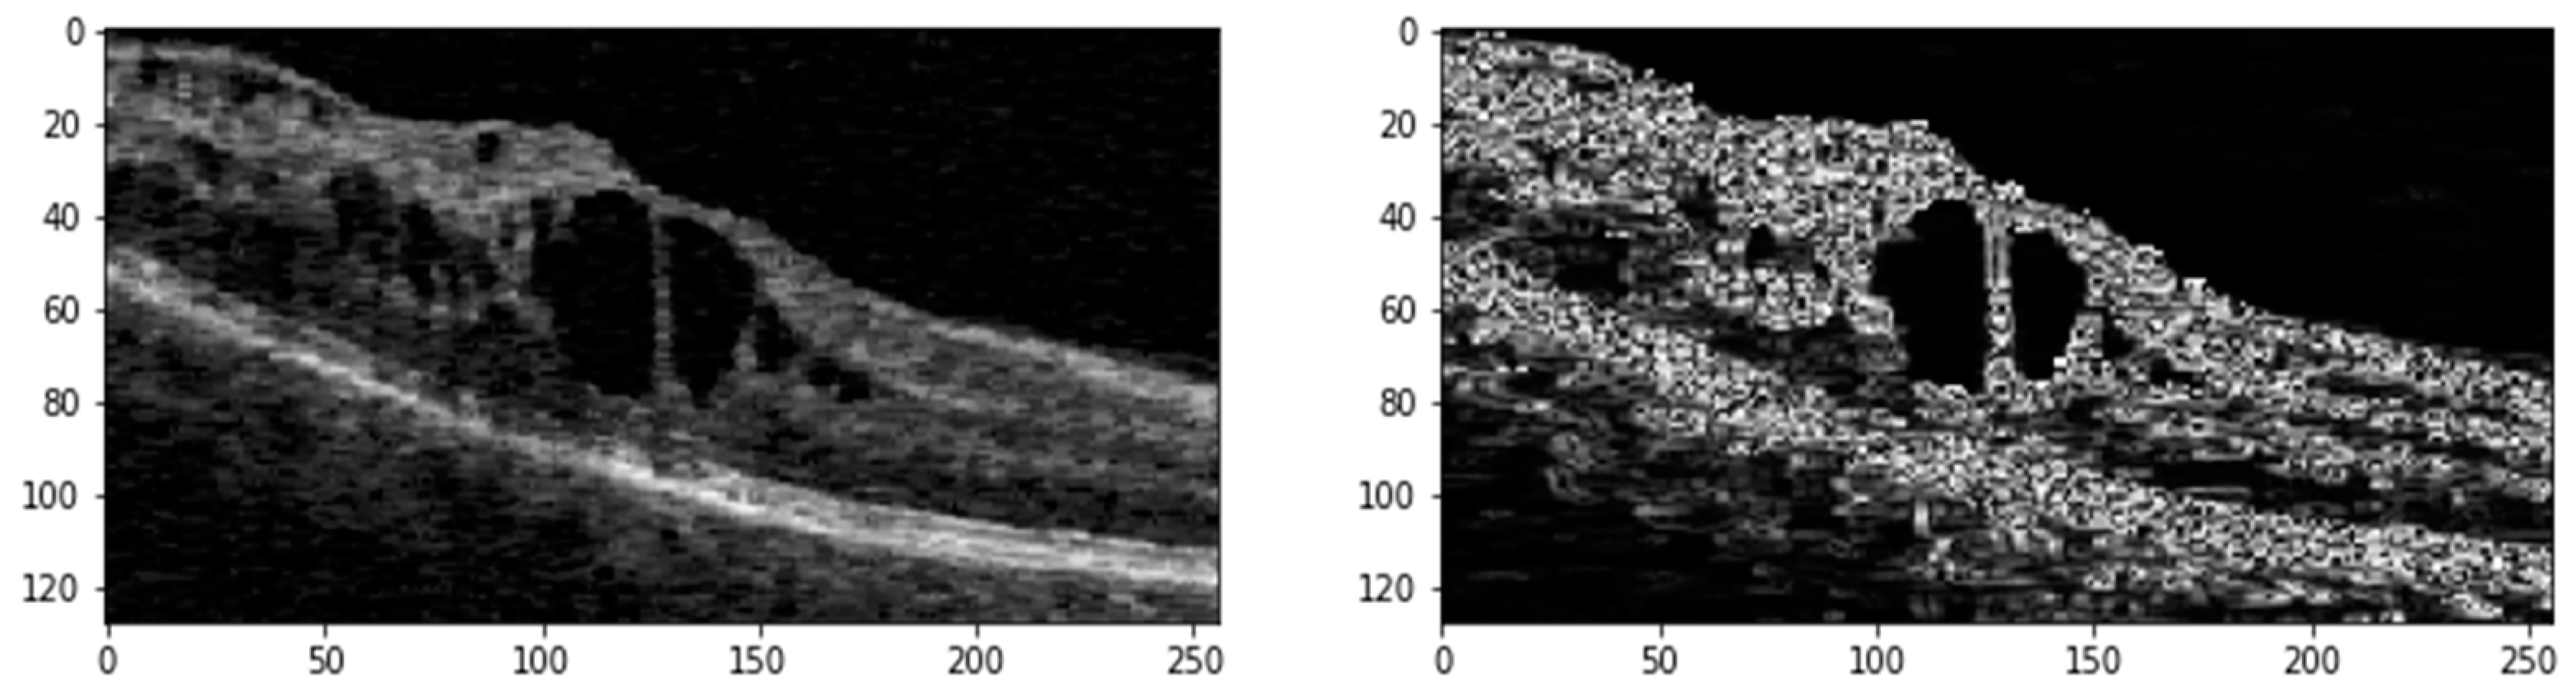

3.2. Pre-Processing

OCT scans from different datasets are generally 3D (C scans), offering volumetric views of retinal layers. In contrast, B scans are 2D cross-sectional slices taken along a horizontal or vertical axis of the retina, with one axis showing the slice and the other depicting depth. For this study, we extracted B scans from the C scans, along with their corresponding pixel-annotated ground truth masks, to form a 2D image dataset. Regardless of the vendor—whether Cirrus, Spectralis, Nidek, or Topcon—B scans typically contain varying amounts of speckle noise and exhibit contrasting differences. We randomly select one with better contrast from all the extracted B scans. We then apply histogram matching across the entire dataset using this selected B scan as a reference. This process helps standardize the intensity distribution and enhances the contrast of the B scans. The images are subjected to median filtering to reduce random noise following histogram matching. The B scans typically contain a small area of interest (ROI) within the image. To eliminate unnecessary background, we calculate the entropy of the images, filtering out regions that do not contain retinal layers or fluids. This pre-processing step ensures that the data fed into the deep learning model are of high quality and consistency, enhancing the overall segmentation performance. Figure 2 shows the ROI generated from the original image with its edge map after pre-processing.

The pre-processed images (Ιm) undergo further refinement using a median filter. Following this, contrast-limited Adaptive Histogram Equalization (CLAHE) with a clip limit () of 1.37 and gamma correction (g) with a gamma value (γ) of 1.7 is applied to enhance image contrast. Additionally, a linear filter (ψ) based on a multivariate Taylor series with antisymmetric properties is used with a τ value of 1.8 to generate edge maps of the denoised images.

Figure 2. ROI generated from the Original OCT scan (Left) and its Edge map (Right).